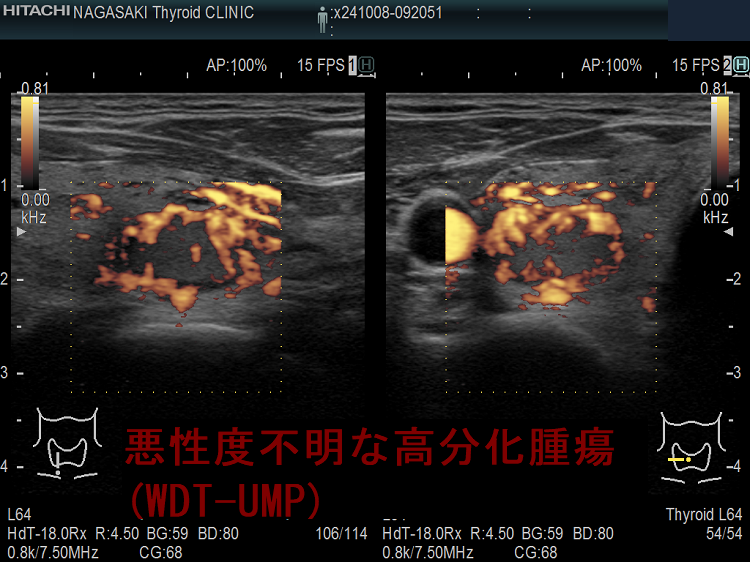

悪性度不明な高分化腫瘍(WDT-UMP);超音波(エコー)画像から判るように、良性濾胞腺腫よりも、腺腫様結節や濾胞型甲状腺乳頭癌に近い見え方です。